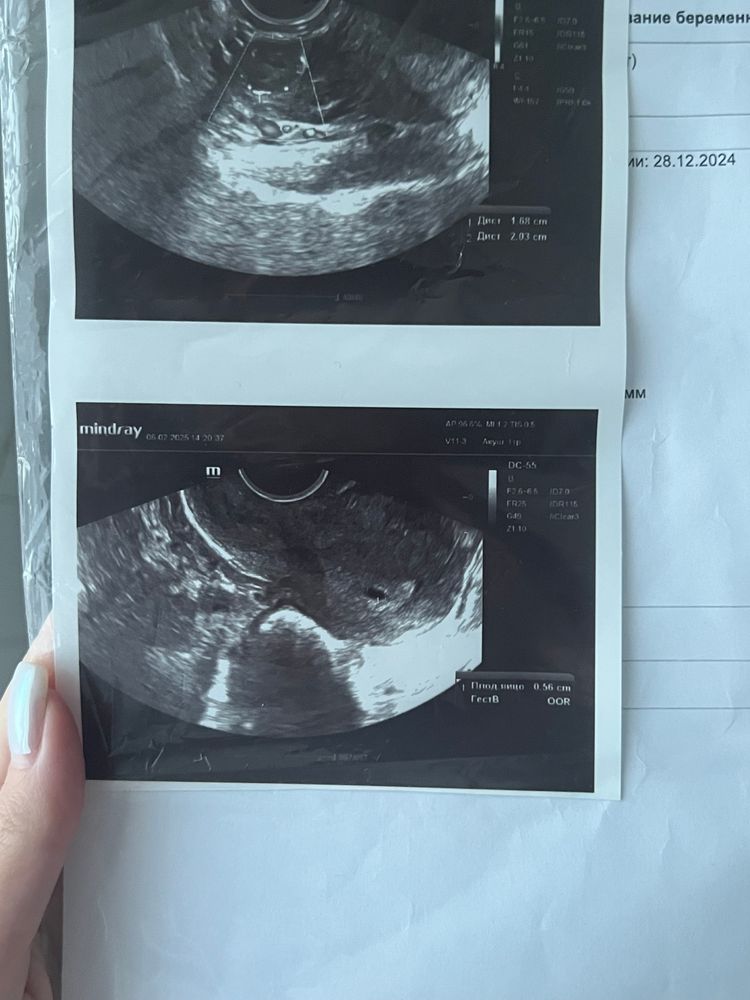

Первое узи🥹

Беременность- 1 триместр ( только до 10 недель)Сходила посмотреть куда прикрепился малышок, он в матке, все хорошо😍 Через 10 дней иду смотреть эмбрион и сердцебиение.

Юлия Ю, 5 недель тоже. Я не хотела идти , думала схожу уже когда эмбрион будет виден, но мне стало интересно😁 плодное яйцо увидят я думаю у вас уже